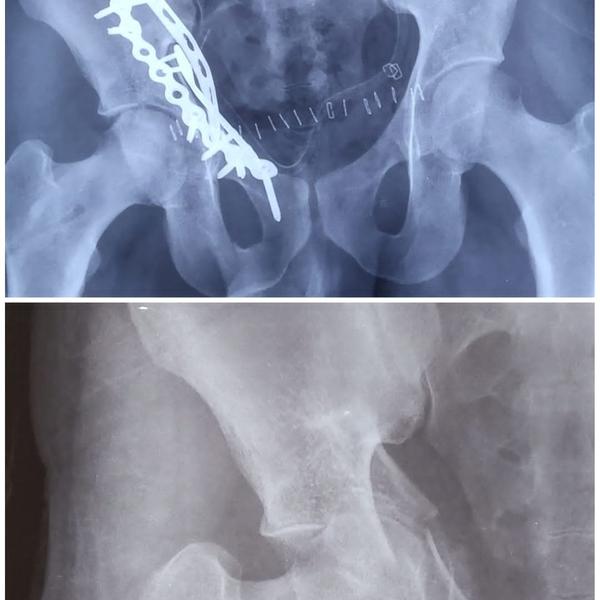

ACETABULUM/ PELVIC FRACTURE SURGERY IN GREATER NOIDA/NOIDA